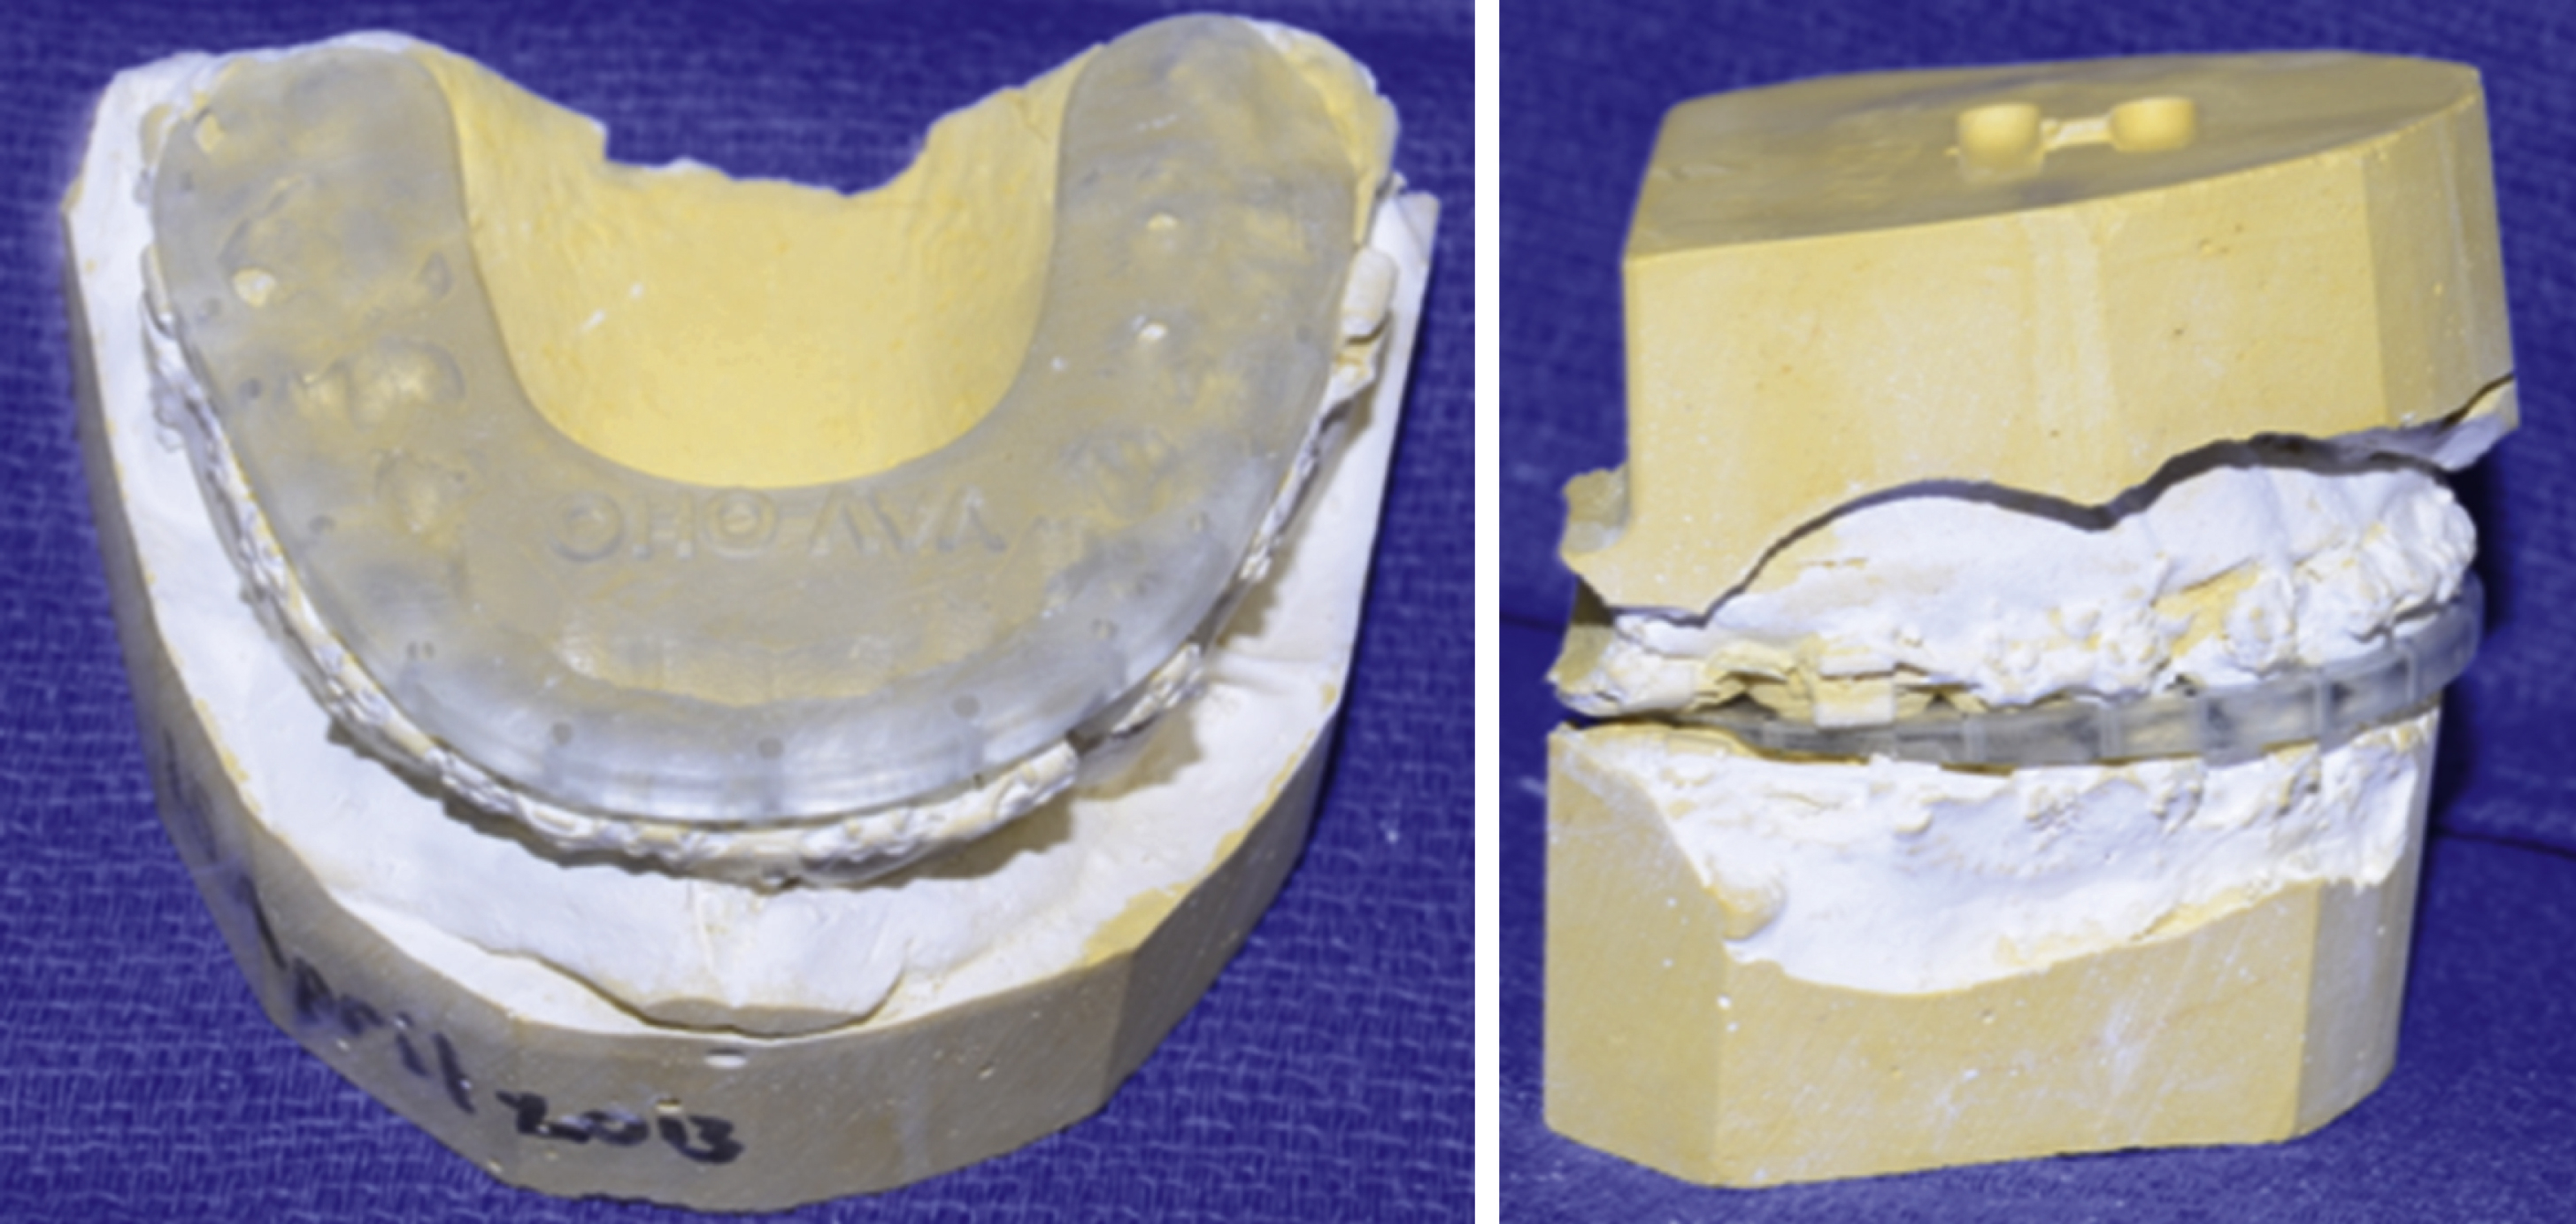

Upon completion of the measurements and record keeping, including a detailed medical/surgical/family history to determine whether the patient is fit to undergo such a procedure, a set of dental impressions should be taken. This is typically performed with an alginate material and appropriately-sized maxillary and mandibular impression trays. The entirety of the dentition, alveolar processes to the depth of the maxillary and mandibular buccal and lingual sulci, hard palate and maxillary tuberosity should be captured in the impression. A dental stone can then be poured into the tray, thus capturing a model of the maxillary and mandibular occlusal relationship for further study. A bite registration should also be taken in the patient’s most reproducible occlusal pattern. The dental models and occlusal bite registration can then be combined with a facebow transfer (an apparatus used to accurately capture the relationship of the maxillary position relative to the skull base and Frankfort horizontal) to mount the exact dentofacial pattern on an articulator. This method is excellent for record keeping and can be used to perform traditional model surgery, although, with the advent of medical modeling and virtual surgical planning, it has become more of an educational tool used to allow trainees to formulate a better idea of the surgical treatment plan.